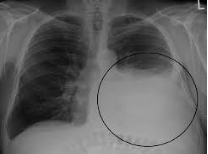

Phải khám thực thể xác định vùng tràn dịch màng phổi, xem phim chụp X-quang ngực thẳng nghiêng và nếu có siêu âm nên sử dụng để xác định vị trí chính xác nhất.

- Xác định vị trí chọc kim (thường ở khoang liên sườn 8 – 9 đường nách sau).